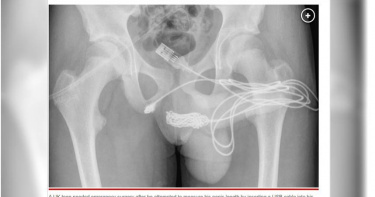

想知道自己有多大 15歲少年「插入USB線」交纏打結GG了

英國一名15歲少年因為想知道自己的生殖器有多大,居然異想天開將USB線插入,結果線在體內纏繞打結,拉不出來,而兩端插孔則露在外面,最後因疼痛不已趕緊就醫。醫師表示,不得不切斷生殖器和肛門之間的部分才成功把線拉出來,經過休養,少年已康復。根據《每日星報》報導,15歲少年將USB線插入自己的生殖器裡,想要測量自己的大小,結果線不幸卡在體內。醫師直言,自己對少年的行為非常困惑,經檢查後發現線完全纏繞住打不開,線的中間部分留在尿道內,而兩端插孔則從尿道口突出。USB線打結。(圖/醫學期刊網站Science Direct)醫師透露,少年身體健康,並沒有精神病史;起初,醫師嘗試拔出USB線是失敗的,後來不得不切斷生殖器和肛門之間的部分,以便他們可以從下面接觸到USB線,最終順利將異物拿出,所幸經過休養,少年已康復。報導指出,性實驗和滿足,以及潛在的精神障礙,被認為是尿道和膀胱內異物滯留的主要原因,治療的方法因對象的形狀、大小以及插入的材質而有所不同。

少年為測長度「整條USB傳輸線塞尿道」 在體內打結!血尿急送醫

英國15歲少年竟為了「測量長度」,異想天開將USB傳輸線插入陰莖內部,沒想到傳輸線在他體內嚴重打結,造成他根本無法靠自己取出,還出現血尿情況;緊急被送醫後,醫生只能將少年陰囊與肛門之間的肌肉切開一個洞,再將傳輸線糾結的線段取出,再從尿道口拔出剩餘的線段。根據《鏡報》報導,這起奇異的事件被刊登在醫學期刊《SCIENCE DIRECT》上,這名15歲的少年因為出現血尿,被母親帶到醫院就醫,直到母親離開診間後,少年才坦承他做了一場「性實驗」,因此故意將USB傳輸線從尿道插入,結果導致傳輸線在體內打結無法取出。報告寫道「患者是一名身體健康的青少年,沒有精神病史。USB線的2個端口從尿道突出,而打結的線中間部分仍留在尿道內」。英國15歲少年竟將USB傳輸線塞進尿道。(圖/翻攝自《SCIENCE DIRECT》)為了將糾纏嚴重的USB傳輸線取出,醫師只好緊急動手術,報告解釋「在可觸及異物的部分上,做一個縱向的陰囊切口,並且通過深層的肌肉組織,進行仔細的切割」,接著再將傳輸線前端從尿道拉出。幸運的是,這名少年手術後恢復良好出院,並在2週後將導管全數拔除。醫師將USB傳輸線剪斷後取出。(圖/翻攝自《SCIENCE DIRECT》)報告表示,將異物插入尿道口的案例並不罕見,臨床上還見過將縫針、大頭針,甚至是開心果的殼,導致患者在排尿時造成疼痛、血尿、勃起疼痛,或是排尿困難;泌尿科醫師補充表示,這種情況並不罕見「性實驗、性慾滿足,以及潛在的精神障礙,被認為是將異物塞進尿道的主要原因」,醫師同時警告,根據插入的方法,物體的大小、形狀,可能導致延遲性併發症,嚴重可能導致復發性尿道感染、尿道狹窄,或是膀胱穿孔等,可能需要進行重大重建手術。

想量自己下面多長 傻男孩做這事急送醫「拉出一條浴血USB線」

最新一期醫學期刊《泌尿科病例報告》近日收錄一個相當罕見的個案,英國一名15歲男孩為了測量自己的下面有多長,不過並不是拿一把尺去計算刻度,反倒是拿一條USB線往自己的尿道裡塞,導致整條線卡在裡頭無法取出,最後只好緊急送醫處理,經過手術後,醫生也從他的尿道裡拉出一條浴血USB線。《泌尿外科病例報告》提到,這名15歲英國男孩因好奇心作祟,於是把一條USB線塞入自己的尿道裡面,結果那條線就這樣纏繞在他的下體,即便多次想取出,但卻無法成功,直到男孩開始尿出血尿後,家人便將他送往倫敦當地一間醫院;根據報導,男孩看診時要求在母親不在場的情況下,才願意與醫生交談,並且承認自己幹了這樣的事情。根據X光報告顯示,男孩的體內的確塞了一條超長的USB線,不過這不能用土法煉鋼的方式直接將其拉出,醫生決定在生殖器以及肛門之間開了一個小孔,接著把轉接線打結的位置剪掉,取出後再把剩餘的電線從尿道拉出體外,最後男孩也順利康復,隔天就出院了,不過他仍需在兩周後回診進行後續掃描。外科醫生拉黑姆(Amr Raheem)提到,在私處插入異物會導致一系列併發症,恐出現尿道感染甚至是尿道發炎的情況,雖然不清楚為何有人會使用這種侵入式的測量方法,但拉黑姆認為,這些行為通常源自於性好奇、酒後性行為、邊緣性人格障礙、分裂情感性障礙以及雙相人格障礙等等,不過值得一提,該名男孩是相當正常的青少年,沒有精神疾病史。男孩將USB線塞入自己的尿道裡,送醫後透過手術成功取出。(圖/翻攝自紐約郵報)